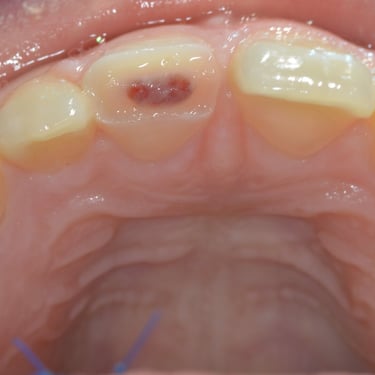

Pulpitis Crónica Hiperplásica

La pulpitis crónica hiperplásica es una inflamación de la pulpa con crecimiento excesivo de tejido pulpar a través de una caries abierta.

Los pacientes notan un tejido rojo que sobresale de la cavidad dental.

El tratamiento incluye la eliminación del tejido afectado y un tratamiento de conducto. Es crucial tratar la caries para evitar infecciones adicionales.